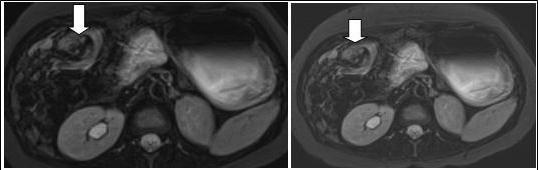

Figure 2B.Axial contrast-enhanced MRI scans show characteristic whirpool appearance of bowel and mesentery wrapping around superior mesenteric artery

Axial contrast-enhanced MRI scans show characteristic whirpool appearance of bowel and mesentery wrapping around superior mesenteric artery

Figure 3.Coronal reformatted image shows contrast agent–filled small bowel on right

Coronal reformatted image shows contrast agent–filled small bowel on right

A 28 weeks and 4 days pregnant, 29 years-old female, known for an L4-L5 discopathy and a past history of surgery for appendicitis at the age of 10 (right-positioned appendix, not perforated), consulted with vomiting and abdominal pain in the epigastric region. Eating and drinking had become impossible at that point. Blood tests revealed pathologically elevated white blood cells count (11.4 G/l for a normal value of 4-10 G/l) and elevated hepatic tests. Preeclampsia and HELLP syndrome were ruled out, as were frequent causes for hepatitis (virus, medicines, auto-immunity). Abdominal echography did not reveal any sign of cholecystitis or pancreatitis and testing for urinary cause was negative. The second blood tests revealed a worsening of the hepatic tests, reason why the patient underwent a cholangio-MRI. This test did not reveal any biliary lesion but volvulus was suspected due to apparent intestinal malrotation. Obtruction was confirmed by gastroscopy (without scope) and situated at the level of the jejunum. Final confirmation of obstruction and its position in the abdomen was also obtained through intestinal MRI (see Figure 2A, Figure 2B, Figure 3). During this time, the patient never displayed any gynaecological signs and foetal echography revealed a foetus with cephalic position, weighting 1300g and a posteriorly inserted healthy placenta with a Manning score of 10/10. The patient was referred for surgery. She underwent an exploratory laparoscopy that revealed multiple adhesions of the small intestine. Volvulus of the small intestine was identified just at the level of the duodeno-jejunal angle, situated on the right side of the aorta. Removal of the adhesions was attempted but ended up causing a small lesion of the small intestine, prompting the transformation of the laparoscopy into an open laparotomy. The laparotomy revealed a volvulus of the small intestine with common mesentery, with encircling of the caecum, the last part of the ileum and the beginning of the jejunum by the omentum. Resolution of the volvulus showed absence of intestinal rotation at the duodeno-jejunal angle, confirming the presence of malrotation. Mesentery was repositioned (without Ladd’s procedure) and fixation of the right colon to the right peritoneum was performed. The small intestine, which showed no sign of ischemia, was sutured and adhesions were completely removed. A few hours after the surgery, the patient presented with uterine contractions every two minutes and uterine ultrasonography showed a 33mm cervix. Tocolysis was immediately given with good results and the contractions definitely ceased and did not reappear two days later when treatment was stopped. During her stay, the patient presented with left basal pneumonia that was treated with antibiotherapy. She completely recovered during the following days and was then discharged with no further complication. The rest of her pregnancy went without any other complication and the patient delivered with instrumentation (Kiwi-sucker) at the age of 40 weeks and 0 days due to a suspect cardio-tocogramm and absence of delivery progression. Both baby and mother were healthy and they were then discharged with no further complication

In that aspect, small bowel volvulus should always remain in the differential diagnosis in front of a pregnant woman presenting with abdominal pain during pregnancy, especially one like ours that was known for a previous surgery for appendicitis (a possible reason for the presence of the adhesions). Radiologic diagnosis of small bowel volvulus can be done by several technics. Plain abdominal film can be used, showing sometimes a typical pattern of dilated loops, but more often showing a normal radiological pattern due to a proximal position of the volvulus (with the loops being filled with liquid). Evidences on CT-scan are the presence of dilated bowel loops, intramural gas and the “whirlpool sign” (Cong et al, 2014; Shui et al, 2011)4, 12, but the use of technics exposing the foetus to radiations is debated. However, in their review, Cong et al 4emphasized the fact that those technics (and particularly plain radiography) are considered safe for the mother as well as for the foetus (Cong et al, 2014)4. MRI is also safe and extremely precise in the diagnosis of small bowel obstruction (Vassiliou et al, 2012)13, sometimes also showing the “whirlpool sign” (Kouki et al, 2013)7 and ultrasonography has been reported to be useful in some instances (Cong et al, 2014)4 but it can also remain completely negative. In our case, while cholangio-MRI suggested the diagnosis, final diagnosis was given by intestinal MRI, showing a possible role for this technic in some unusual cases, in which doubts about the diagnosis or about the state of different abdominal structures remain. However, in cases in which clinical symptoms, laboratory and more basic radiological (plain abdominal film of CT-scan) are highly suggestive of this pathology, exploratory surgery should be started at the earliest time possible.